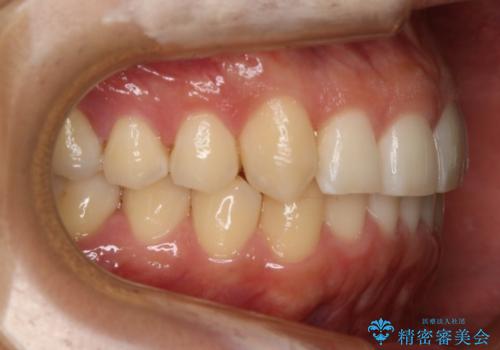

インビザラインで八重歯の治療

八重歯と噛み合わせえお治す必要がありましたが、抜歯を必要とするほどの状態ではなかったため非抜歯プランで治療を開始しました。

マウスピースとマイクロインプラントを組み合わせることで、抜歯をしなくても歯並びを治すためのスペースを作ることができます。奥歯から順に移動させていくので前歯に変化が出るまでには時間がかかりますが、その分健康な歯を抜歯することなく理想的な歯並びを手に入れることができます。